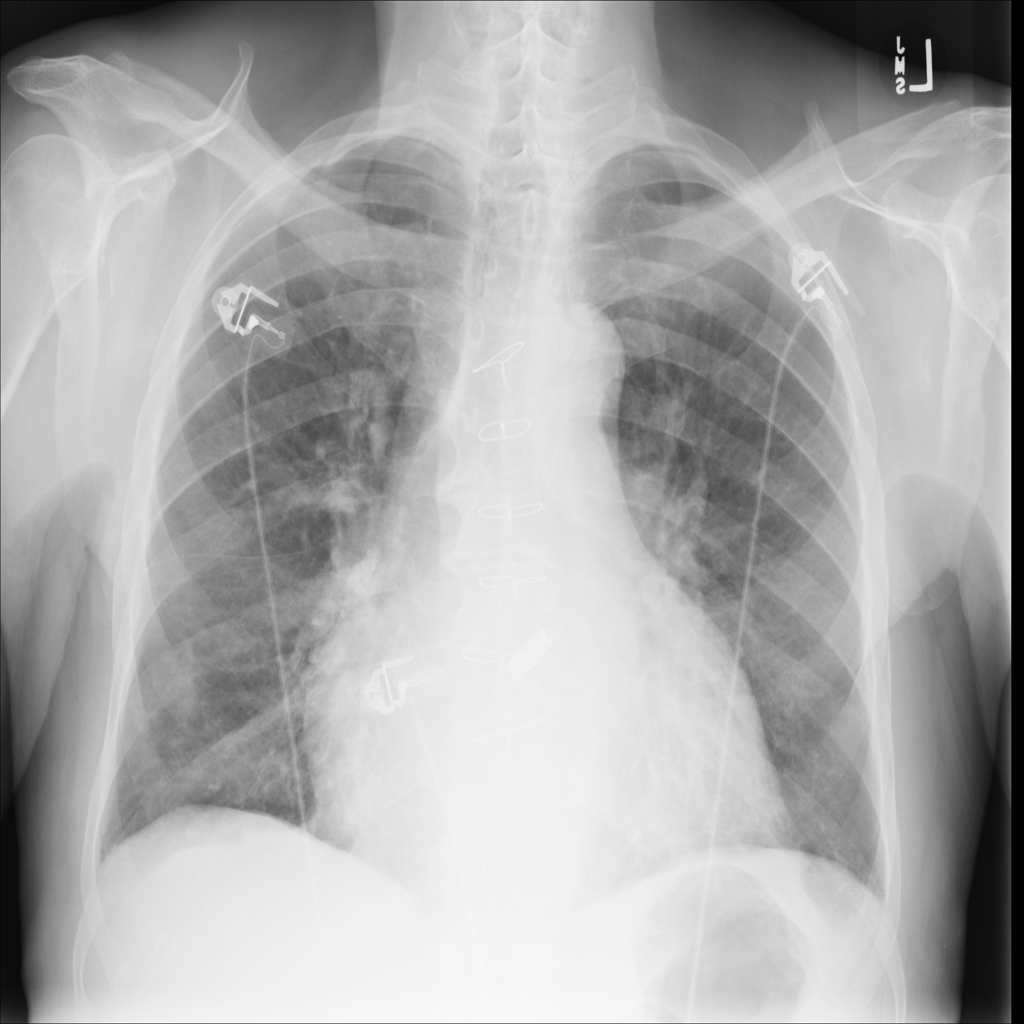

Nodule

A nodule is a small rounded opacity in the lung or chest field. It is a descriptive imaging finding that can be benign or more concerning depending on size, appearance, and context.

Showing up to 90 reference images for Nodule.

PAT-FB8F · IMG-000Nodule

PAT-FB8F · IMG-000

PA